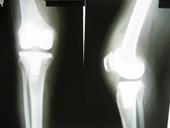

Arthriis of both hips pre op Arthriis of both hips post op Arthritis knee valgus deformity pre op Arthritis knee valgus deformity post op